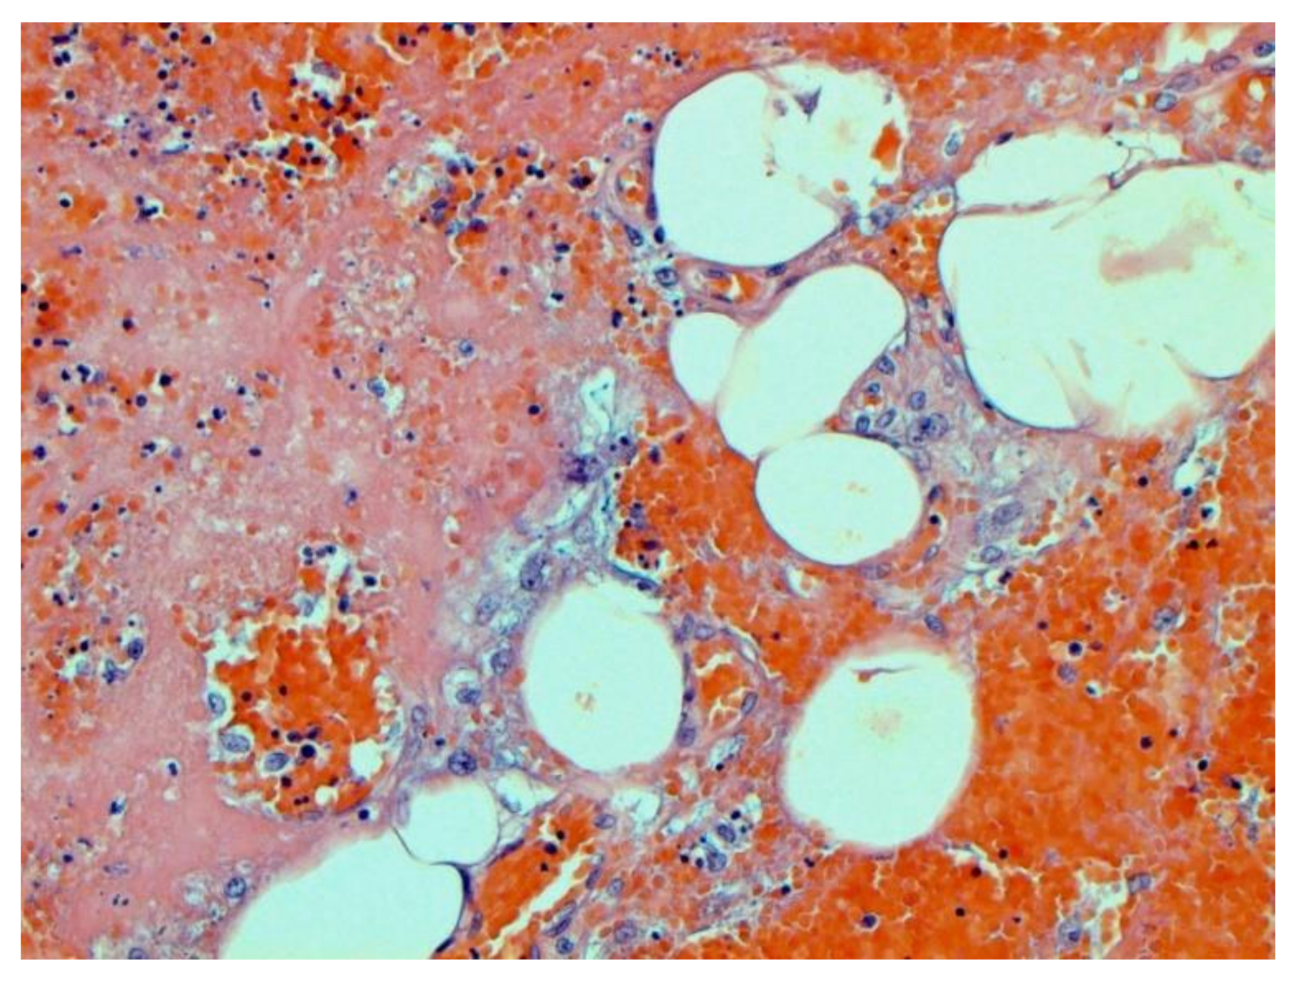

The main morphological substrate of respiratory insufficiency is diffuse alveolar damage. The term viral pneumonia, widely used in the clinic, essentially reflects its development. In turn, severe diffuse alveolar injury is synonymous with the clinical concept of “acute respiratory distress syndrome” (ARDS). In the pathogenesis of ARDS, without a doubt, the most important role is played by the damage to the microcirculatory bed, the genesis of which requires further study, but direct viral damage is most likely. COVID- 19 is characterized by a pronounced fullness of the capillaries of the interalveolar septa, as well as branches of the pulmonary arteries and veins, with erythrocyte sludge, fresh fibrin, organizing blood clots, and intrabronchial, intrabronchiolar, and intra-alveolar hemorrhages, which are a substrate for hemoptysis, as well as perivascular hemorrhages (Figure 8). Pronounced alveolar hemorrhagic syndrome is characteristic of most cases, up to the formation, in fact, of hemorrhagic infarcts (although true hemorrhagic infarcts are not uncommon). Pulmonary blood clots are important to distinguish from thromboembolism, as pulmonary embolism (PE) is also characteristic of COVID-19. Thrombosis of the pulmonary arteries sometimes progresses to the right parts of the heart, and thrombosis of the arteries of various organs with the development of their infarcts (myocardium, brain, intestines, kidneys, and spleen) is described. This distinguishes changes in the lungs in COVID-19 from those previously observed in influenza A/H1N1. Despite the pronounced hemorrhagic syndrome, significant deposits of hemosiderin are not observed.

Figure 8.

Edema and perivascular hemorrhages in lung. H-E ×100.